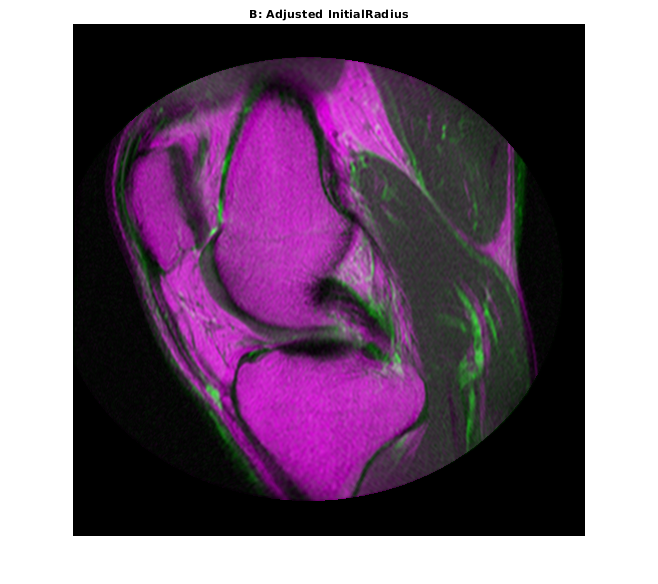

InitialRadius свойство оптимизатора управляет начальным размером шага, используемым в пространстве параметров, чтобы совершенствовать геометрическое преобразование. Когда многомодальные регистрационные проблемы не сходятся параметрами по умолчанию, InitialRadius хороший первый параметр должен настроить. Запустите путем сокращения значения по умолчанию InitialRadius масштабным коэффициентом 3,5.

optimizer.InitialRadius = optimizer.InitialRadius/3.5; movingRegisteredAdjustedInitialRadius = imregister(moving,fixed,'affine',optimizer,metric); imshowpair(movingRegisteredAdjustedInitialRadius,fixed) title('B: Adjusted InitialRadius')

Корректировка InitialRadius оказанный позитивное влияние. Существует значимое улучшение выравнивания изображений на верхних и правых краях.